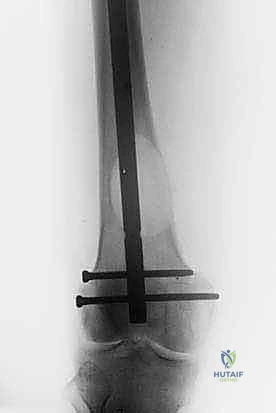

1. التثبيت الوقائي الداخلي (Prophylactic Internal Fixation)

إذا أظهرت الأشعة أن العظم ضعيف جداً وعلى وشك الانكسار، يقوم الدكتور هطيف بوضع أسياخ نخاعية معدنية (Intramedullary Nails) أو شرائح ومسامير متطورة داخل العظم لتدعيمه ومنع الكسر قبل حدوثه. هذه الجراحة الاستباقية توفر على المريض آلاماً مبرحة ومضاعفات خطيرة.

| جسم عظم الفخذ أو الساق | كسر مرضي كامل أثناء التحميل. | التثبيت بمسمار نخاعي تشابكي (Intramedullary Nailing). |